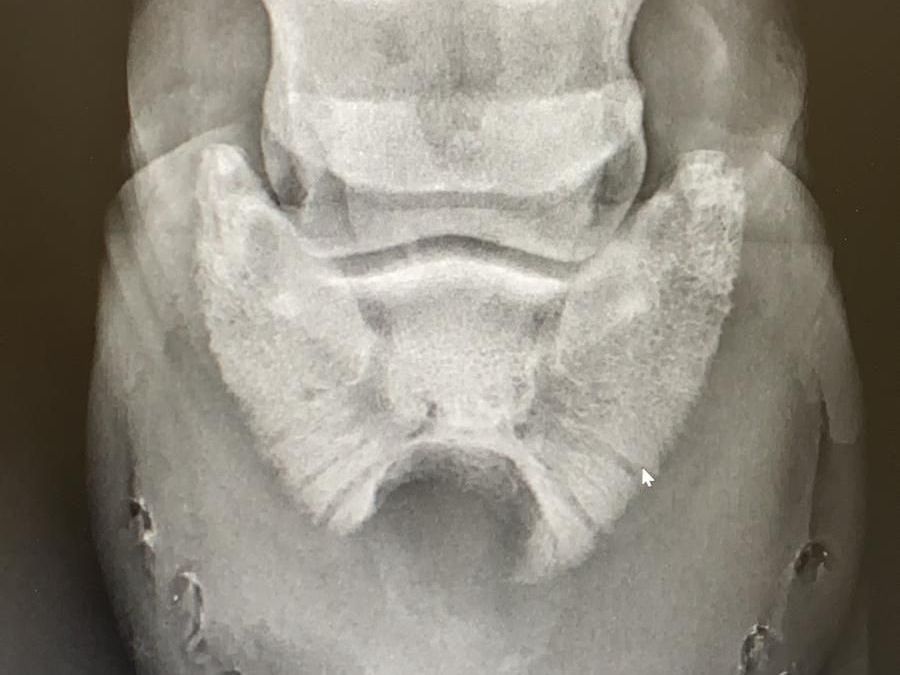

Dieses Pferd wurde vorgestellt mit immer wiederkehrenden Entzündungen und Eiteraustritt am Kronrand. Nach einer Kontrolle des Hufs mittels Röntgenbildern wurde die Diagnose Hornsäule gestellt.

Auf den Bildern sieht man, wie die Hornsäule einen Halbmond in das Hufbein geschliffen hat. Wann immer es geht, mache ich einen Zugang in der Sohle und oben am Ende der Hornsäule eine Öffnung in der Hufwand. Dann kann ich die Hornsäule rausfräsen, ohne die Hufwand zuviel zu schädigen / schwächen.